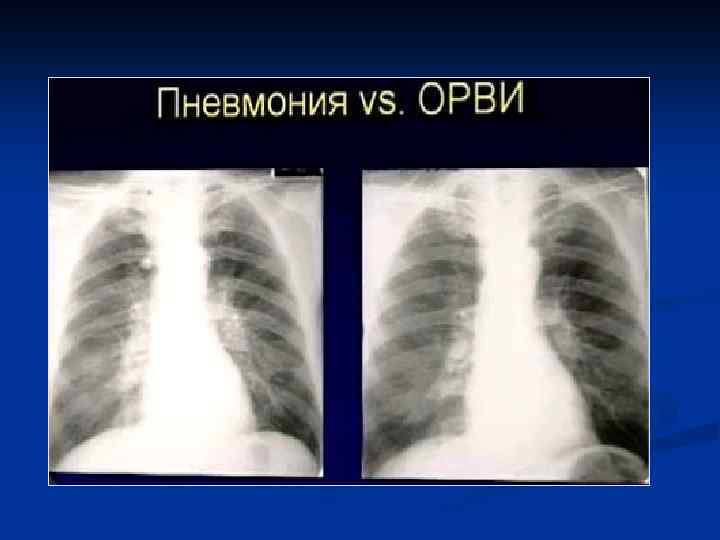

Интерстициальная пневмония

Интерстициальная пневмония n n n n Хуже диагностируются чем паренхиматозные Чаще – постгриппозные Вяло текут ОАК – почти норма Субфебрилитет Жалобы на недомогание, сухой кашель, вялость Это продуктивное воспаление (лечится тяжело)

Интерстициальная ПН - ретикулярные = сетчатые изменения легочного рисунка - преимущественно центральным = прикорневым распределением - могут быть очаговые сливающиеся уплотнения легочной ткани

Клиническая картина Типичная - острое начало - лихорадка - кашель с обильной гнойной мокротой, влажные хрипы - боли в грудной клетке Атипичная - постепенное начало - сухой непродуктивный кашель - недомогание - першение в горле - миалгия - головные боли